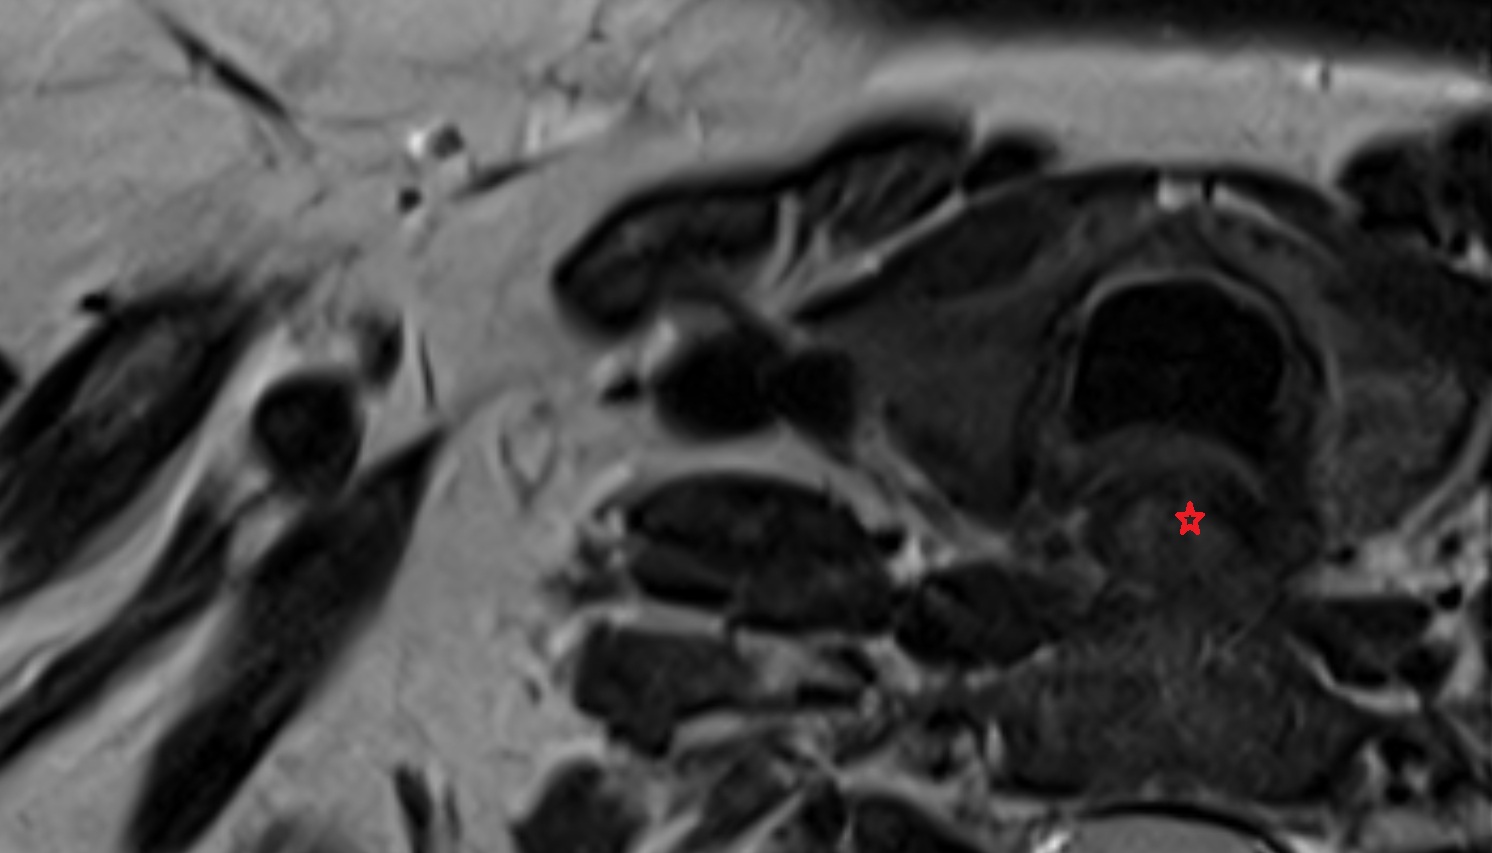

- Temporomandibular joint

- Mandibular condyle

- Mandibular fossa

- Articular disc of temporomandibular joint

- Articular eminence